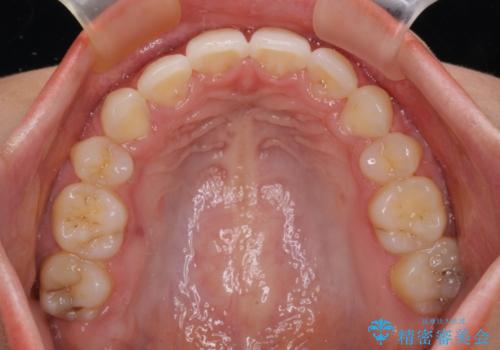

- 口元の突出感を気にして来院された患者様です。

上下左右の第一小臼歯4本を抜歯して口元を下げる治療計画としました。

3年半ほどで終わる予定でしたが、途中引っ越し、出産、引っ越し、出産を繰り返し、なかなか来院することができず、装置を外すまでに8年以上の期間がかかってしまいました。